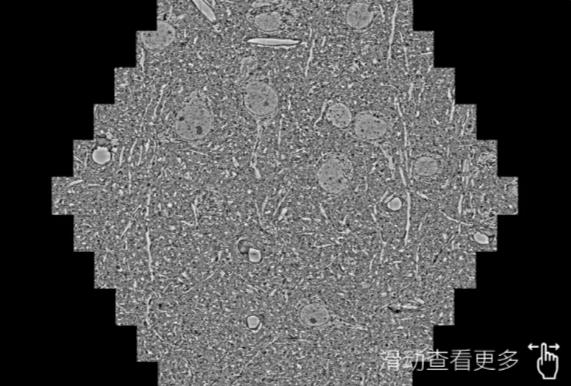

鼠脑切片。左图使用鄂州蔡司鄂州扫描电镜MultiSEM706对165μmx143pm面积区域成像,耗时仅需1.5秒。右图为鼠脑切片中30μm区域放大效果。样品由芝加哥大学B.Kasthuri提供。

使用蔡司高速鄂州扫描电镜MultiSEM对1mm²人脑皮层组织进行高分辨成像,并对其中的各种细胞结构进行三维重构分析。左图展示了2x3mm²组织平面中锥体神经元的三维重构效果。右图显示了局部体积神经元三维重构。图像由哈佛大学chtman实验室提供,渲染图由D. Berger 制作。